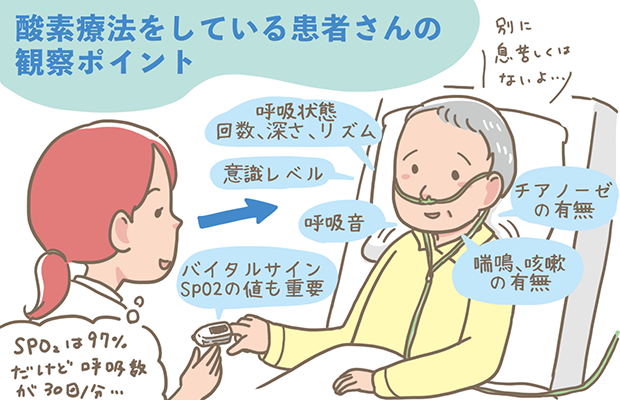

酸素療法の基礎知識!目的、合併症、看護のポイントについて解説!レバウェル看護 お役立ち情報。

酸素療法の基礎知識!目的、合併症、看護のポイントについて解説!レバウェル看護 お役立ち情報。